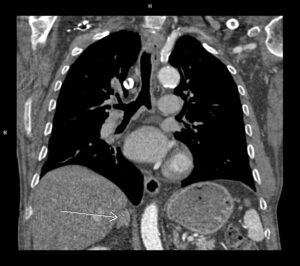

Figura 3: reconstrucție volumică (VRT) din examinarea inițială cu evidențierea stenozei severe de la nivelul arterei descendente anterioare

Figura 8: reconstrucție volumică (VRT) din examinarea inițială cu evidențierea stenozei severe de la nivelul arterei circumflexe